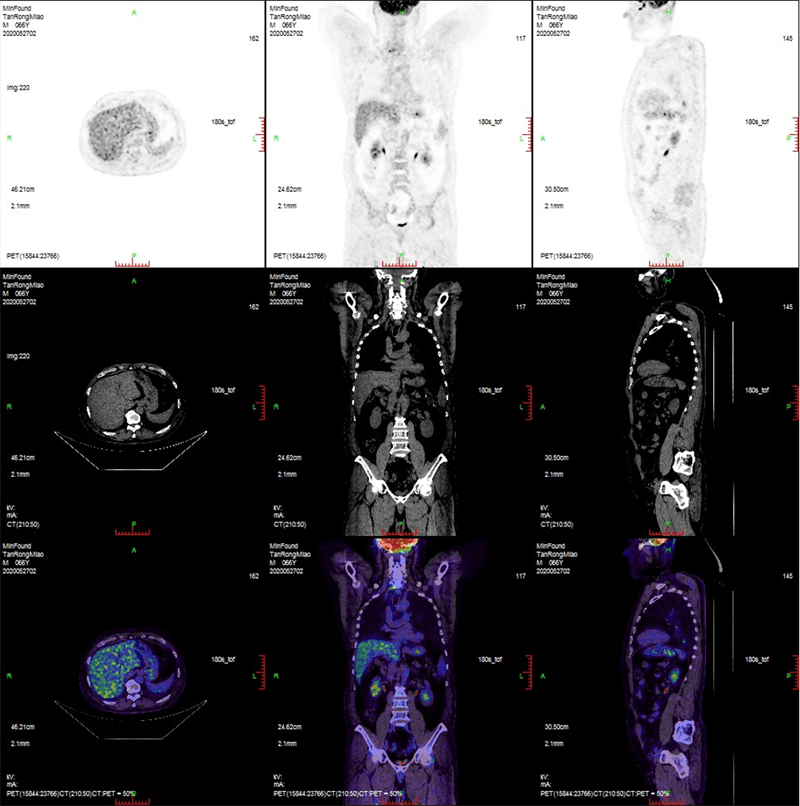

1675934369.png